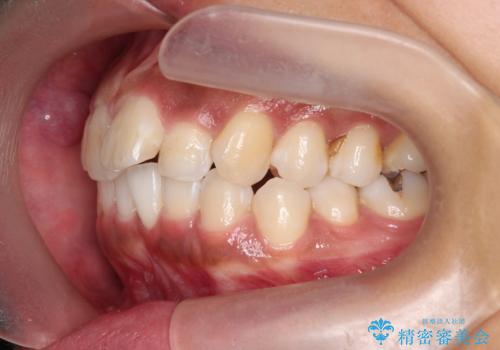

出っ歯感のある前歯を治したい、抜歯をしないマウスピース矯正

- 前歯のガタつき、突出感のある前歯の改善を求めて来院されました。

前歯の角度を改善し審美性を高めるとともに、奥歯のガタつきも並べ直すことで安定した咬合関係の確立を目指します。

歯列の側方拡大をしっかりと行ったことで歯を抜かずに前歯の角度をしっかりと改善することができました。